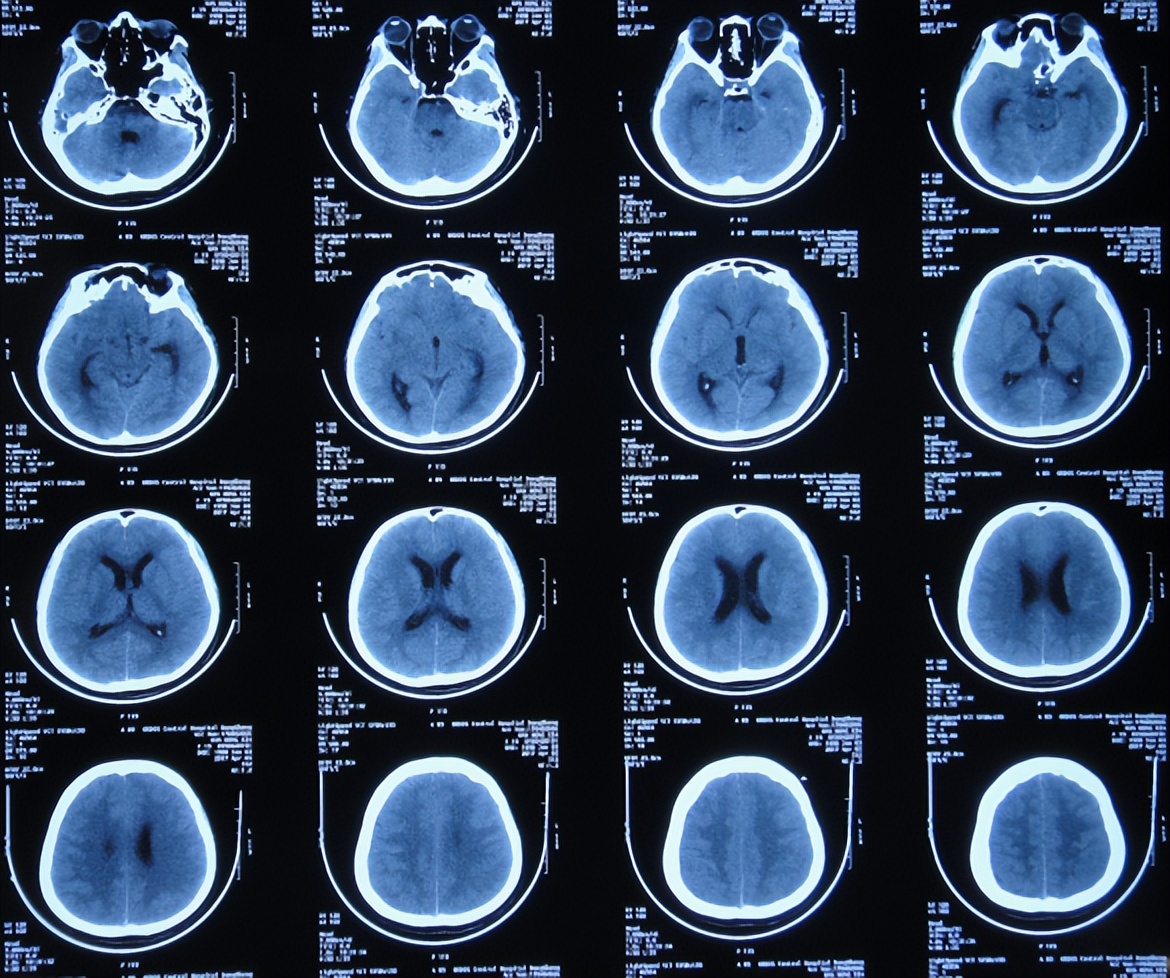

2017年4月2日(发病后13天),就诊于第2家的陕西省神木县某医院急诊外科,检查期间突发四肢软瘫、意识丧失、大小便*禁失**,查脑CT( 图-2 )后紧急收入ICU。

图-2: 2017年4月2日脑CT

行腰椎穿刺检查脑脊液常规:细胞高达1548×106 /L,淋巴细胞百分比56.8%,蛋白高达2266mg/l,糖1.15mmol/l,医院考虑结核性脑膜炎,家属当天晚上紧急将患者转至第3家的内蒙古的鄂尔多斯市某三甲医院。